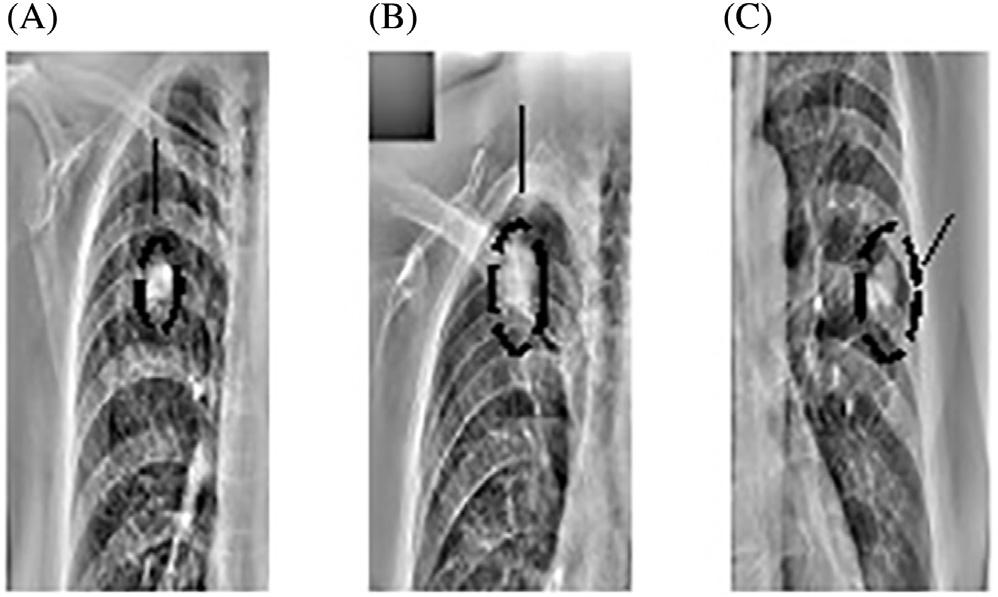

对于每个尺度 $s_k$,使用归一化拉普拉斯算子计算X光图像 L 的尺度空间表示。 图14.13 展示了该步骤的输出结果。可以看出,真实的结节能够在 σ = 4.6661处被正确检测到。

然而,观察到出现了大量假阳性。需要寻找方法来减少假阳性(图14.14)。不同尺度下结节检测结果叠加显示。注意,斑点通常在多个连续尺度上被检测到。对于每幅尺度图像,

σ = 2.5198, (B) σ = 3.4290,和 (C)σ = 4.6661)